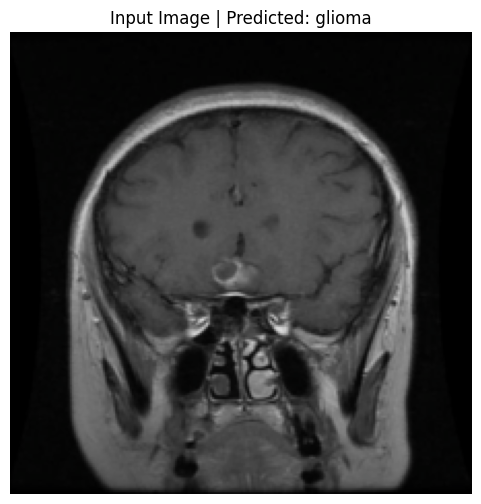

print(f"\nDisplaying input image #{image_index} which was predicted as: {predicted_label}")

plt.title(f"Input Image | Predicted: {predicted_label}")

Displaying input image #0 which was predicted as: glioma